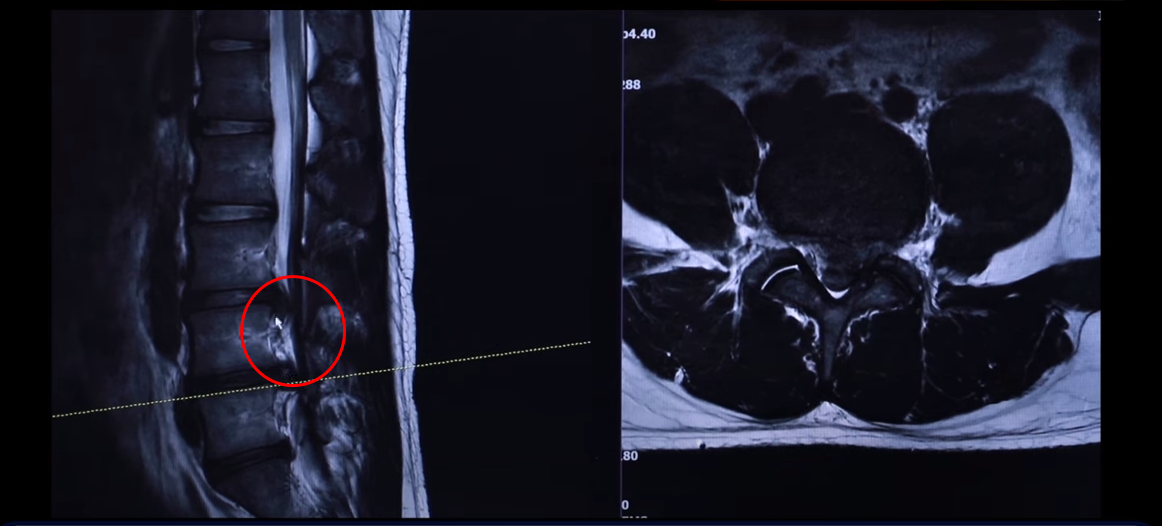

여기 24세 남자 환자분 MRI 보도록 하겠습니다. 옆에서 보는 MRI 보시다시피 어마어마하게 지금 심하게 터져 있습니다. 일반인이 보셔도 아실 정도로 두 마디가 아주 심하게 터졌고 여기도 약간 밀려 나와 있습니다.

단면을 한번 보도록 하겠습니다. 여기를 잘라서 본 단면인데요. 왼쪽으로 많이 밀려 나와 있죠? 이 한마디만 해도 파열돼서 상당히 많이 밀려 나온 겁니다. 왼쪽 다리가 저리고 아플 수 있습니다.